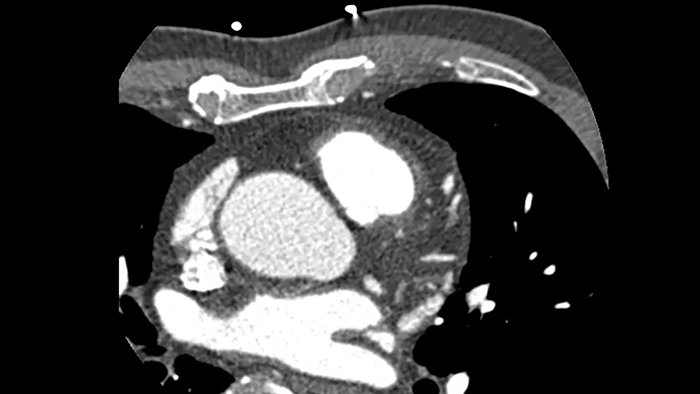

Шестикратное улучшение временного разрешения3 Коррекция контуров коронарных артерий с применением искусственного интеллекта позволяет отследить и учесть движение коронарных артерий, представив максимально четкий результат без артефактов от движения.

Решение проблем визуализации сердца

Визуализация сердца без артефактов движения улучшает качество изображения при высокой частоте сердечных сокращений

ContinueУсовершенствованная реконструкция с компенсацией движения для визуализации сердца без артефактов движения с улучшенным анализом коронарных сосудов

3. Внутренние исследования компании Philips о влиянии снижения артефактов от движения коронарных артерий на эффективное временное разрешение. Шестикратное улучшение временного разрешения 29 мсек было достигнуто с использованием КТ со скоростью вращения рентгеновской трубки 0,35 сек. При использовании КТ со скоростью вращения 0,27 сек было зафиксировано одиннадцатикратное улучшение временного разрешения 12,3 мсек